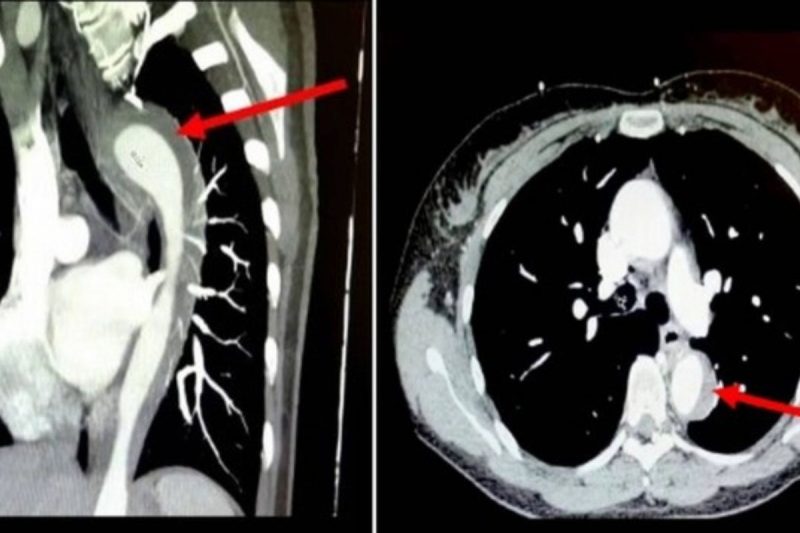

Caso é considerado incomum e pode ser fatal – Foto: Reprodução/InternetCaso é considerado incomum e pode ser fatal – Foto: Reprodução/Internet

Os médicos descobriram que a mulher teve uma AAS (Síndrome Aórtica Aguda), um espectro de condições potencialmente fatais. Eles descobriram um vazamento na aorta, artéria que transporta sangue pelo corpo.